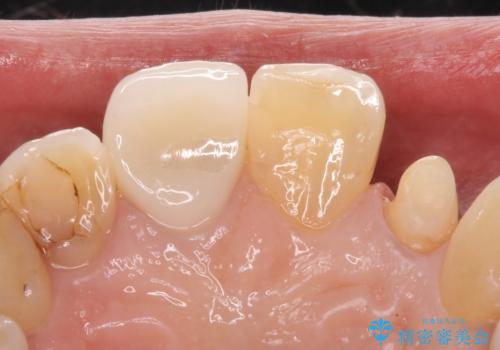

- 継ぎ接ぎになった前歯を綺麗にしたいとのことで来院されました。

継ぎ目のないクラウンで修復処置していきます。

- 左上2 仮歯+ジルコニアクラウン:11,000円+121,000円費用は治療当時の料金となります

精度の良い被せ物を装着することで、違和感のない自然な見た目を獲得することができます。